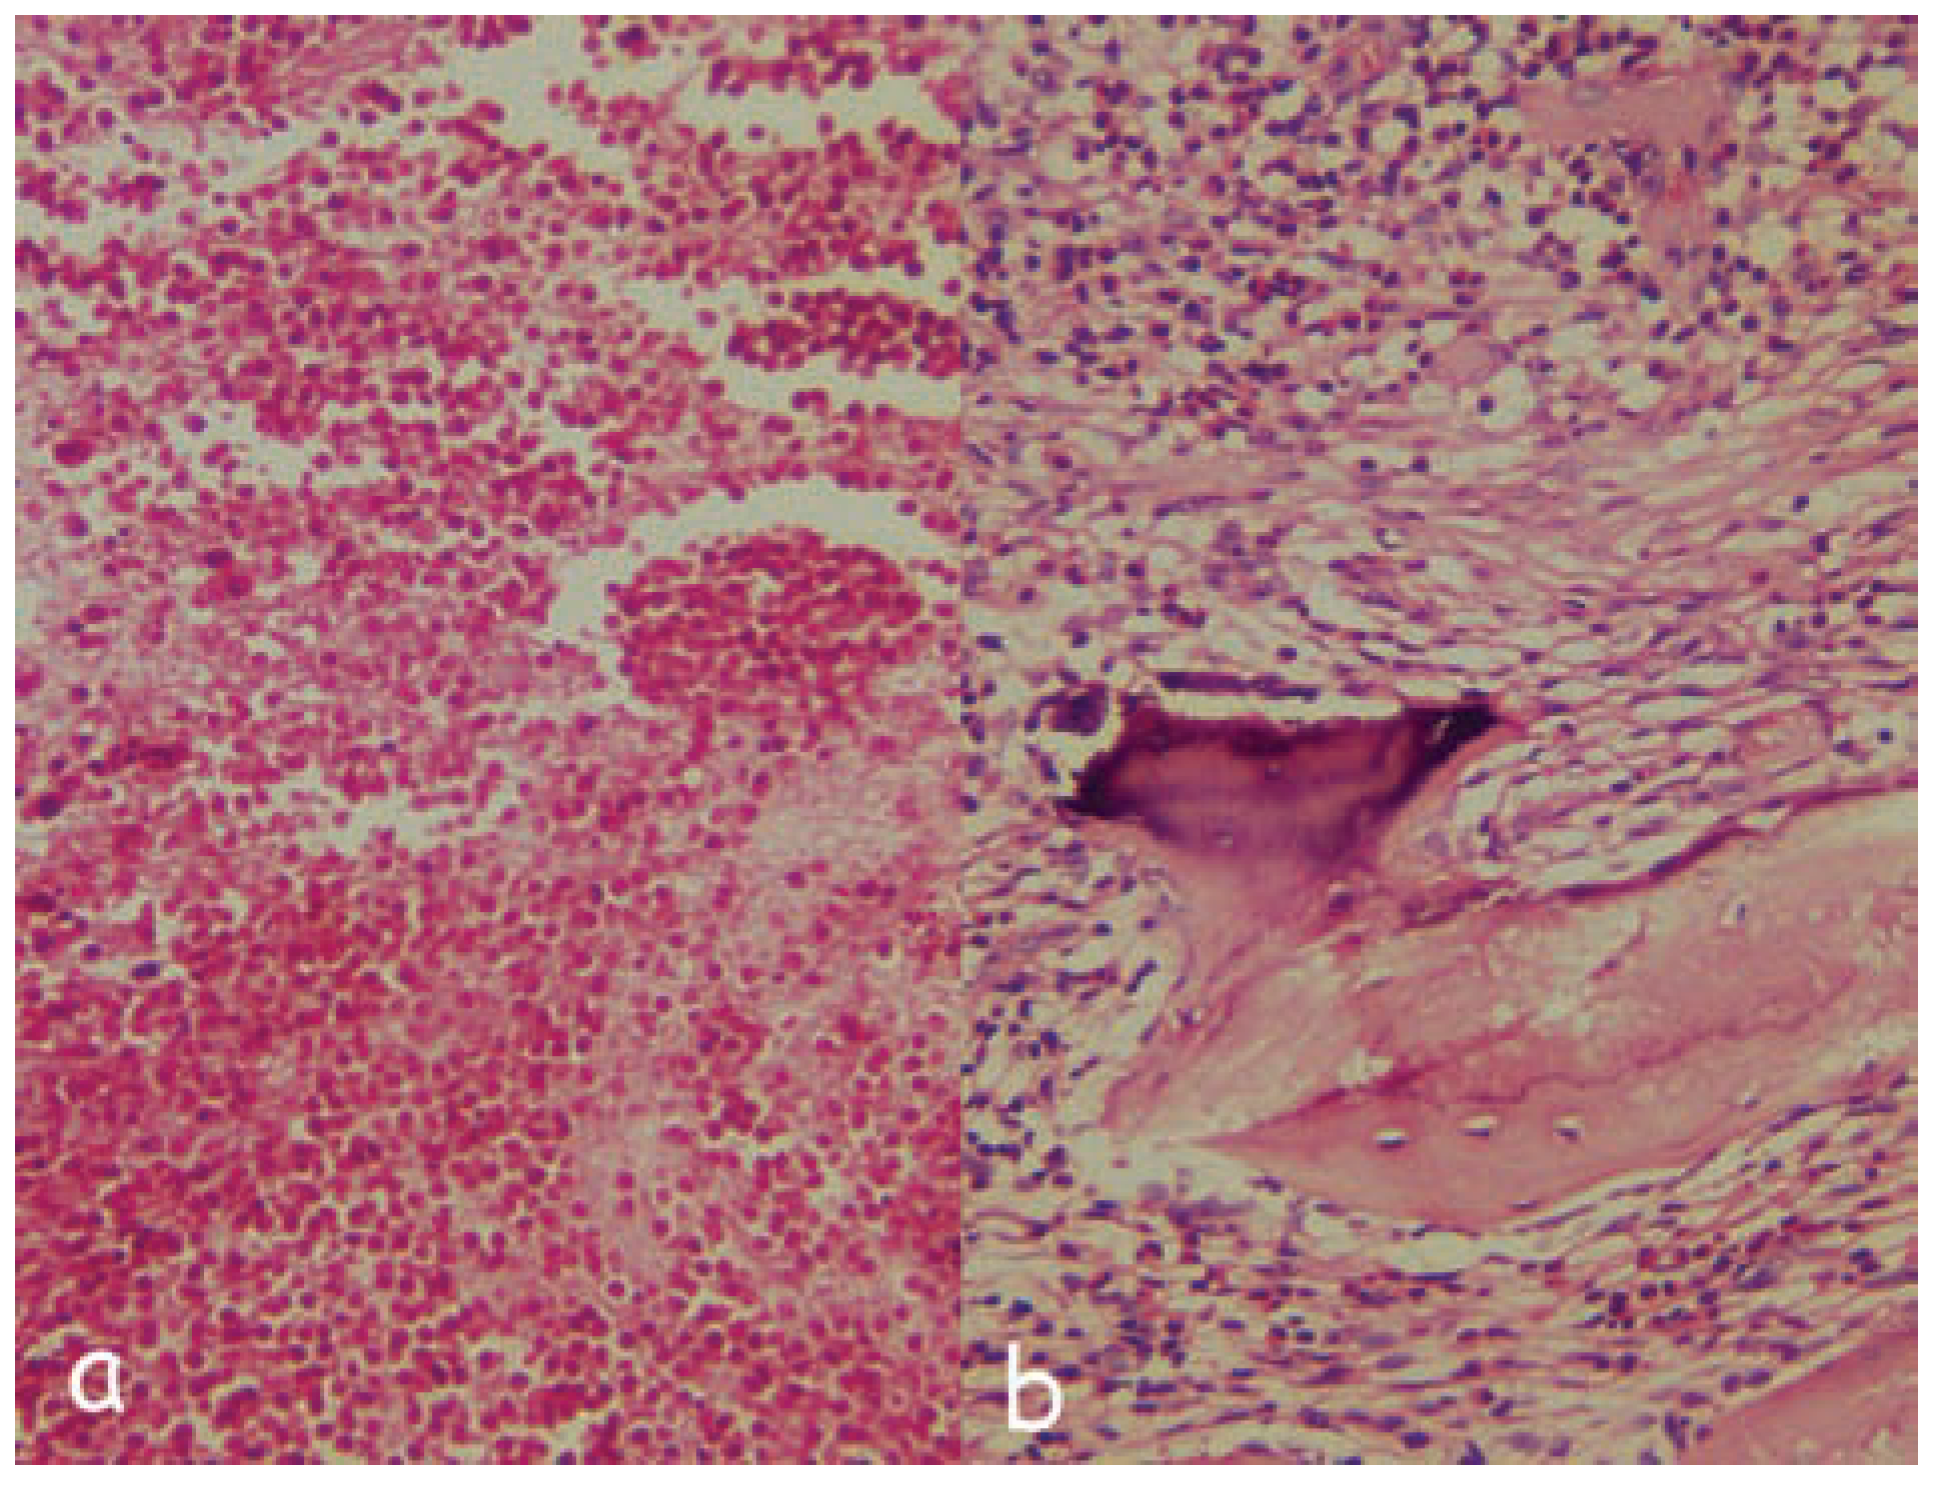

:Case Presentation